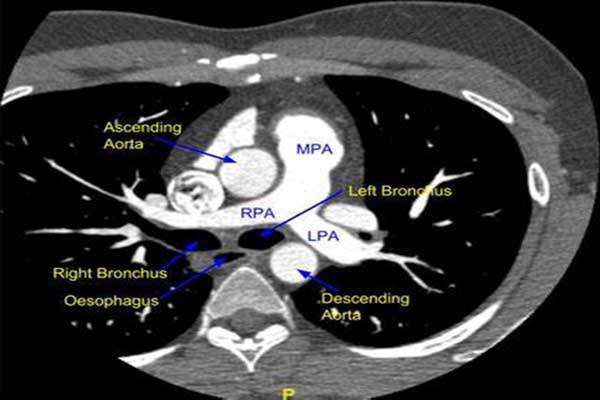

Structural heart disease interventions represent a new branch of percutaneous treatments covering a wide range of congenital and acquired diseases that were previously treated surgically or simply not addressed. The term structural heart disease has been widely used to refer to a group of noncoronary heart diseases ranging from septal defects to acquired valvular disease. With his tireless efforts, Dr. Dan Sraow worked closely with the administration at Dignity Health East Valley to start the Structural Heart Program at Chandler Regional Medical Center. This new branch of percutaneous intervention has several distinguishing characteristics: